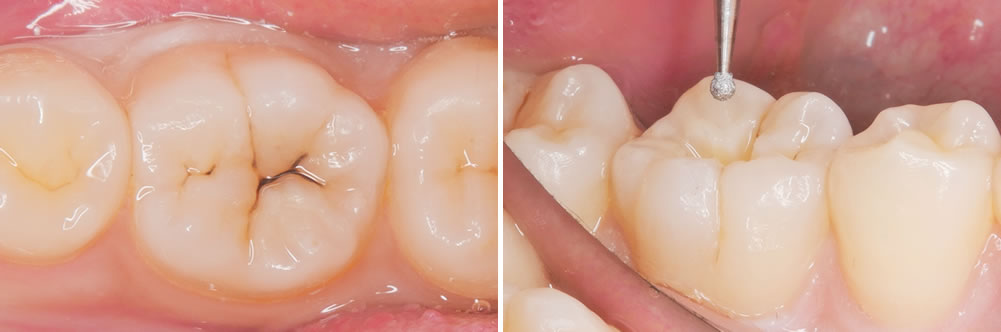

こちらの患者さまは、右下奥歯の虫歯を主訴に来院されました。

右下の奥歯に黒い部分が見受けられます。範囲は小さいため、出来るだけ削らないように先端の小さな器具を用いて丁寧に虫歯を除去していきます。

虫歯治療の除去

う蝕検知液を用いて丁寧に虫歯を取り除いていきます。

さらに奥にある虫歯は、より小さな器具を用いて削る範囲が大きくなりすぎないようにします。

治療完了

形態修正と研磨を行い、治療が終わりました。